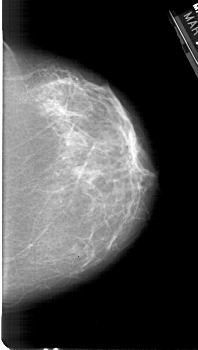

A_1387_1.RIGHT_MLO